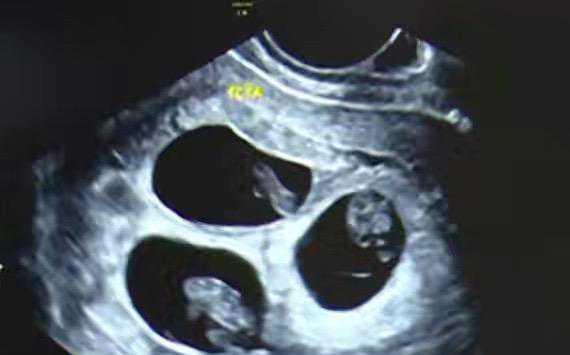

正文 试管婴儿能选择性别吗? admin V管理员 /2025-12-27/198 阅读 1227 第三代试管婴儿技术是可以实现性别选择的!但非医学需要选择胎儿性别,在我们国家是不允许的~所以,正规有三代资质的生殖中心基本上是不能要求医生选择性别移植的。除非找专门的绿色通道,才有实现的可能。除此以外,都是没办法在正规生殖中心进行特需操作的。有些家庭会考虑市面上的试管机构,这种“地下模式”的风险是很大的,比如医疗风险、合同风险等等。所以,建议大家选择正规靠谱的机构,全程正规医院操作,医疗风险可控,医疗过程也更透明! -- 展开阅读全文 --